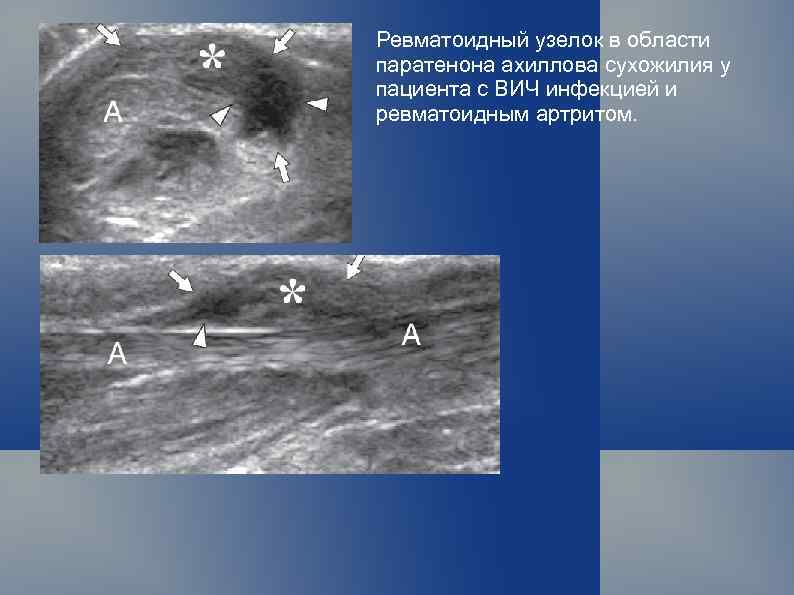

Ревматоидный узелок в области паратенона ахиллова сухожилия у пациента с ВИЧ инфекцией и ревматоидным артритом.